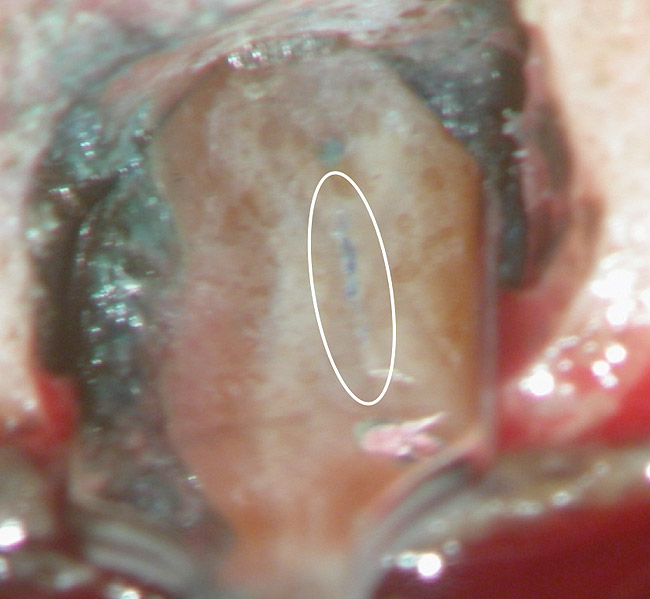

Figure 4a  Tooth No. 30 Nonsurgical root canal treatment had been completed 5 years before. The periapical radiograph revealed periradicular radiolucencies (periapical and in the furcation area).

Figure 4a

Figure 4b  The patient was asymptomatic, and periodontal probing depths were within normal limits; however, a new crown restoration was planned. Nonsurgical endodontic re-treatment was initiated. The intracoronal picture shows the previously treated 4 canals with infected gutta-percha filling.

Figure 4b

Figure 4c  Under high magnification, a furcation canal (Figure 4C) and a third distal canal (Figure 4D) were located.

Figure 4c

Figure 4d  Under high magnification, a furcation canal (Figure 4C) and a third distal canal (Figure 4D) were located.

Figure 4d